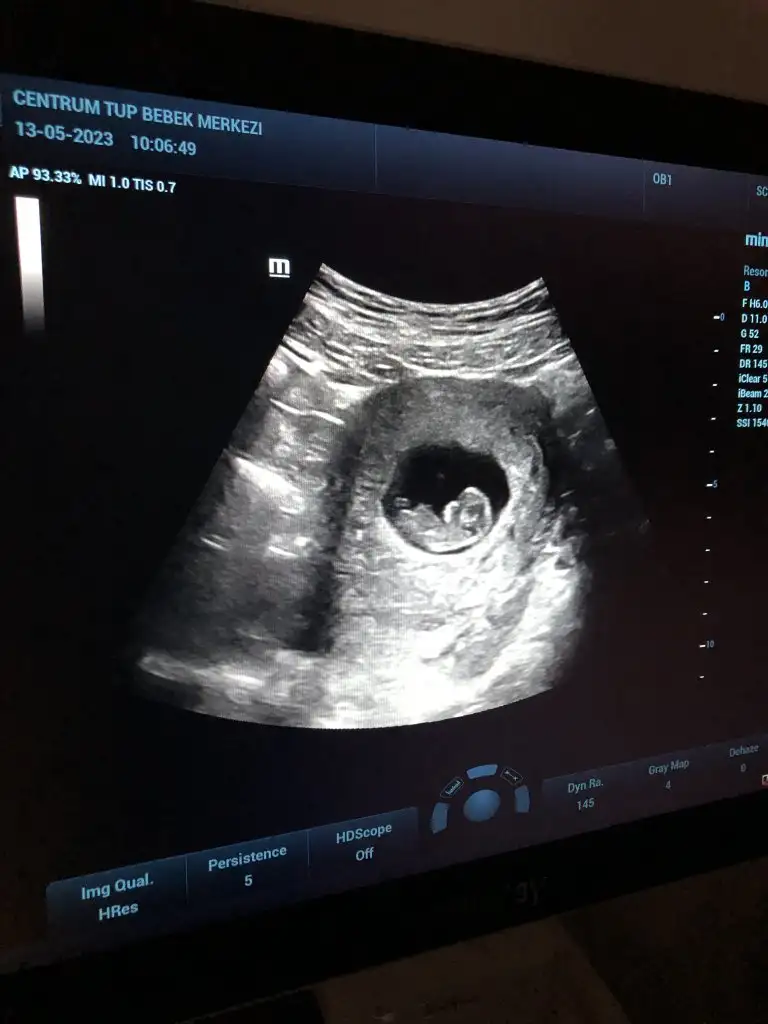

Amin canım 11. Haftaya gireceğiz az kaldıben gördüm canım benımde 5. gün embriyosuydu 8. gün böyle vıkmıstı ama erken gebelık testı alsaydın keske

yaaa teyzesi yesin kocaman olmuş bak hahahaa maşallah yavruma bizde 12. haftaya girdik yarın inşallah cinsiyet öğreneceğimMerhaba teyze

Maşallah canım, ne güzrl bir tane beklerken iki tane bebişin olmuş. Allah bağışlasın bebişleriKızlar merhaba. Çok şükür 10 haftalık olduk bizde. Bugün kontrolümüz vardı ufak ufak hareketlerini gördük. Tek embriyo transferi olmıştı ama ikiz gebelik oluştu, tek yumurta ikizi. Bu hafta nipt testi yaptıracağız sanırım, aranızda yaptıran oldu mu?

Bende bugün 9 haftalık oldum 12. Haftada gideceğim kontrole çok uzun zaman varAllah razı olsun canım, tabi bi taraftan sürekli korku, iyiler mi diye. Allah hepimizin bebeklerini sağlıkla kucağımıza almayı nasip etsin

Evet bana da geçmiyor zaman hiçç. Daha da hissedemiyoruz hareketlerini o da korkutuyorBende bugün 9 haftalık oldum 12. Haftada gideceğim kontrole çok uzun zaman var